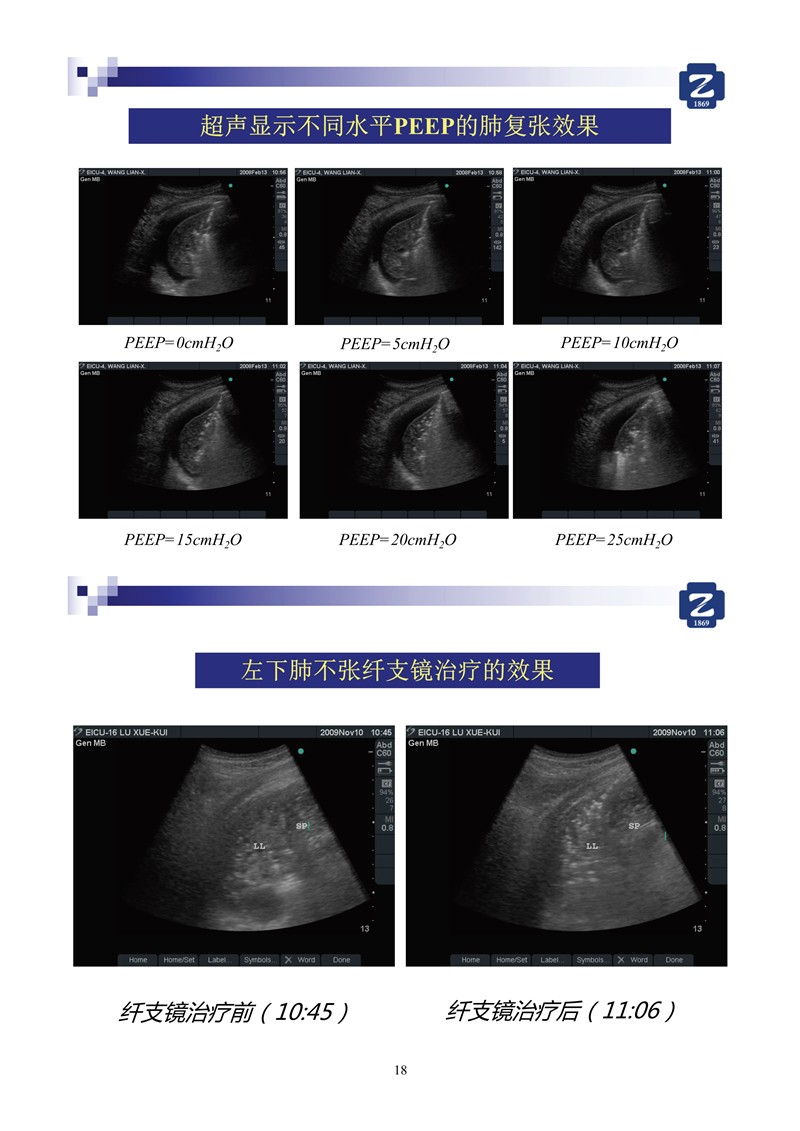

第一版新型冠狀病毒肺炎超聲診斷實用手冊(全文)

新冠肺超聲實用手冊(2)_35.jpg